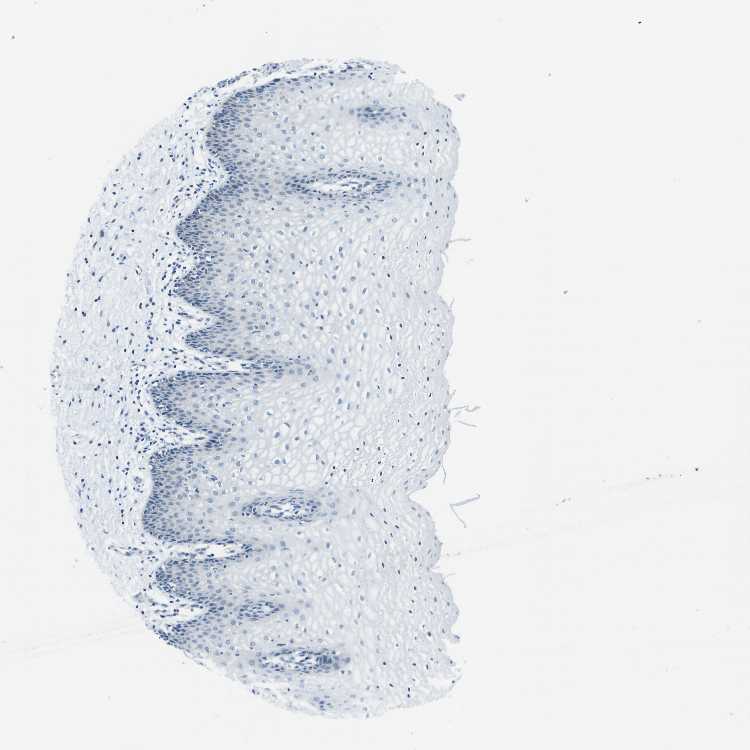

TISSUE PRIMARY DATA VAGINA Show tissue menu

Vagina

VAGINA - Antibody stainingi

Antibody staining in the annotated cell types in the current human tissue is reported as not detected, low, medium, or high, based on conventional immunohistochemistry profiling in selected tissues. This score is based on the combination of the staining intensity and fraction of stained cells.

Each image is clickable and will lead to virtual microscopy that enables deeper exploration of all samples and also displays staining intensity scores, fraction scores and subcellular localization as well as patient and tissue information for each sample.

Antibody HPA039291Antibody HPA044062Antibody CAB017448

Squamous epithelial cells LowLowNot detected